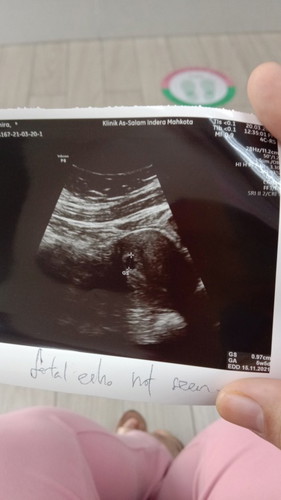

hi momies i nak tanya 20/3 i ade scan untuk tgok week...tapi mase scan dekat dlam kantung tuh i nampak mcm ade kedip²...i nak tanya momies...yg tuh ape yew yg kedip² tuh...sebb doc shak jantung dia...tapi masa nak dengr jntungg still takde bunyii...kenape yew...i need explain...